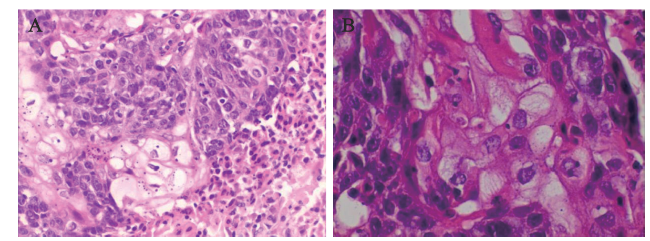

病例1 肿瘤呈浸润性生长,肿瘤细胞排列成大的巢团状,部分巢团中央可见坏死,巢团周边肿瘤细胞多呈基底细胞样,核质比高,细胞异型性明显,中央见散在体积较大、胞质呈多空泡状的皮脂腺分化细胞,符合SC。见图1

图1 一例腮腺SC组织的HE染色结果

注:A示肿瘤细胞排列成大的巢团状,部分巢中心可见坏死(×100);B示巢团周边多见空泡状的皮脂腺分化细胞(×400)。